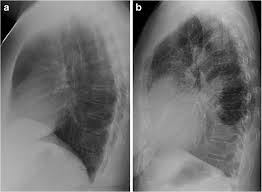

Retrocardiac air space disease. Airspace disease is considered chronic when it persists beyond 4-6 weeks after treatment. Tendency to coalesce near hila. The margins of airspace disease are fuzzy and indistinct.

By early detection and proper evaluation of the abnormal retrocardiac shadows the radiologist may establish the diagnosis before the clinical signs and symptoms of compression of large blood vessels and nerves become. Retrocardiac Air Space Disease. Air space opacification is a descriptive term that refers to filling of the pulmonary tree with material that attenuates x-rays more than the surrounding lung parenchyma.

Airspace disease is considered chronic when it persists beyond 4-6 weeks after treatment. A single retrocardiac air-fluid level on a chest radiograph typically implies the presence of a sliding hiatal hernia. This unusual type of bibasilar atelectasis happens when the lung is trapped as a result of pleural disease while being devoid of air. Airspace disease also known as alveolar lung disease is a generic term thats used to describe abnormalities on chest x-ray or CT. The most common clinical causes of this CT pattern of disease include hypersensitivity pneumonitis sarcoidosis atypical infections eg those caused by Mycoplasma pneumoniae with associated bronchiolitis and acute interstitial pneumonia 25. The 2021 edition of ICD-10-CM J984 became effective on October 1 2020. J984 is a billablespecific ICD-10-CM code that can be used to indicate a diagnosis for reimbursement purposes. And retrocardiac air space disease. Retrocardiac Air Space Disease.

The location retrocardiac - behind the heart shouldnt make a difference. It is the radiological correlate of the pathological diagnosis of pulmonary consolidation. The most common clinical causes of this CT pattern of disease include hypersensitivity pneumonitis sarcoidosis atypical infections eg those caused by Mycoplasma pneumoniae with associated bronchiolitis and acute interstitial pneumonia 25. The particular way the lung collapses can often produce a. Acinar or air-space nodules. CT 5-mm slice thickness in a patient with bilateral consolidation. Tendency to coalesce near hila.